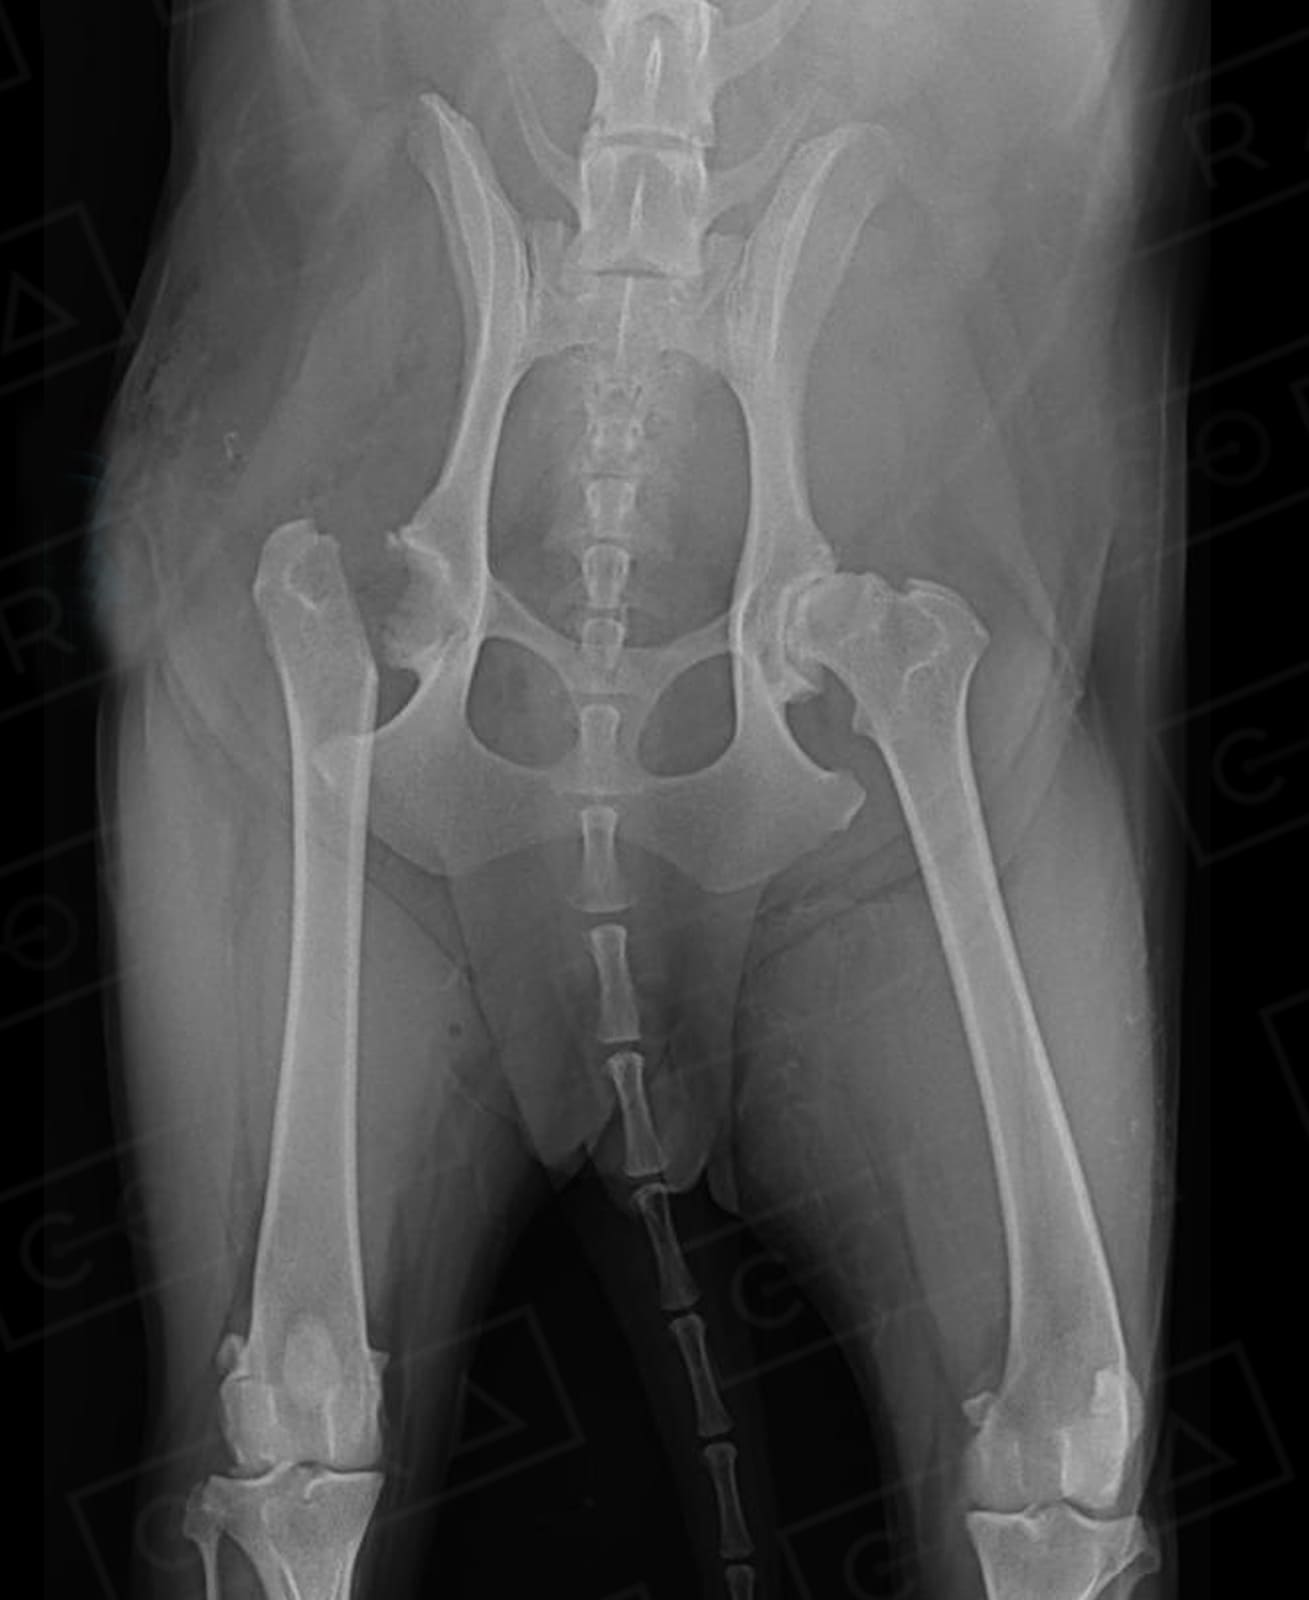

DISPLASIA COXOFEMORAL

A sinais clínicos (DCF) é uma doença de característica genética e poligênica envolvendo uma ou ambas as articulações do quadril, causada pela instabilidade do quadril, levando a incongruência articular e desenvolvimento de osteoartose.

O diagnóstico é baseado na anamnese, exame físico e radiográfico simples. O diagnóstico precoce, em filhotes ainda assintomáticos, pode ser feito por meio do PennHIP, técnica de raio-x por distração articular, que estima o grau de instabilidade do quadril e risco de desenvolvimento de osteoartrose. O diagnóstico precoce possibilita um melhor prognóstico e mais qualidade de vida ao animal.

4. Osteotomia Dupla ou Tripla de Pelve (ODP ou OTP)

Técnica preventiva para cães até 8 meses de idade, usada para aumentar a cobertura acetabular sobre a cabeça do fêmur para impedir ou minimizar a subluxação do quadril e subsequente desenvolvimento da osteoartrose. Vários pré-requisitos são necessários para a escolha dessas técnicas.